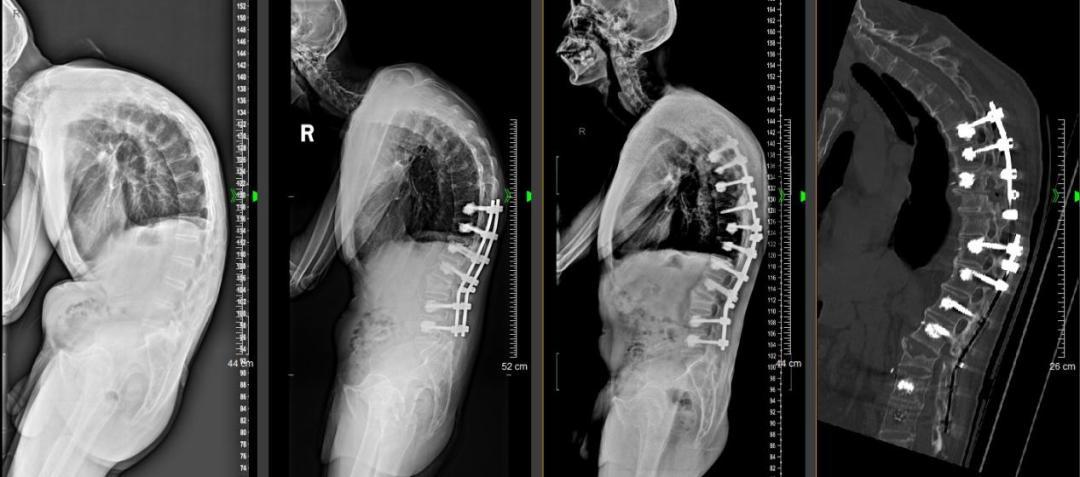

2024年7月赵先生第一次入院,医生为其进行全面检查评估,术前影像学检查提示赵先生脊柱参数严重失去平衡:整体脊柱后凸角度达到113°,其中胸椎后凸92.5°,腰椎后凸20.5°,骨盆后倾,重力线明显前移212mm,颌眉角(指颌眉线和身体垂线的夹角)75°(正常为0度)。严重的脊柱后凸导致赵先生腹部严重皱褶、胸骨凸入腹腔、胃肠等消化器官受压。

术前经过全科疑难讨论,黄敏军最终决定为赵先生实施分期脊柱后凸矫形手术:第一期先实施经腰2椎体四级截骨矫形手术,恢复腰椎前凸,增加腹腔容积、减轻腹部脏器受压,部分改善后凸畸形;术后半年,再行第二期更为复杂的胸椎经椎弓根截骨后凸矫形手术,进一步改善后凸畸形,尽可能获得水平视野、实现平卧睡觉。

2024年7月,赵先生接受了第一次脊柱截骨矫形术。术中体位摆放困难,摆体位共花了1个多小时;严重骨质疏松很容易导致螺钉松动内固定失败,使用骨水泥强化螺钉,增加螺钉把持力才解决这个问题;术中矫形容错率极低,要时刻注意避免脊柱脱位造成脊髓损伤瘫痪。第一次矫形后,赵先生的脊柱舒展了一些,相关症状也得到了缓解。

2025年5月,赵先生入院接受二次脊柱矫形,手术后,他的脊柱终于伸展了。术后查房,黄敏军对患者说:“术前我们精准制订矫形计划,矫形不足会导致你无法获得水平视野,你也没办法实现平卧睡觉,又担心过度矫形导致你以后无法看到脚尖,走路也会受影响,我们努力寻找平衡点,看你现在的行走姿态,我想我们成功了。”